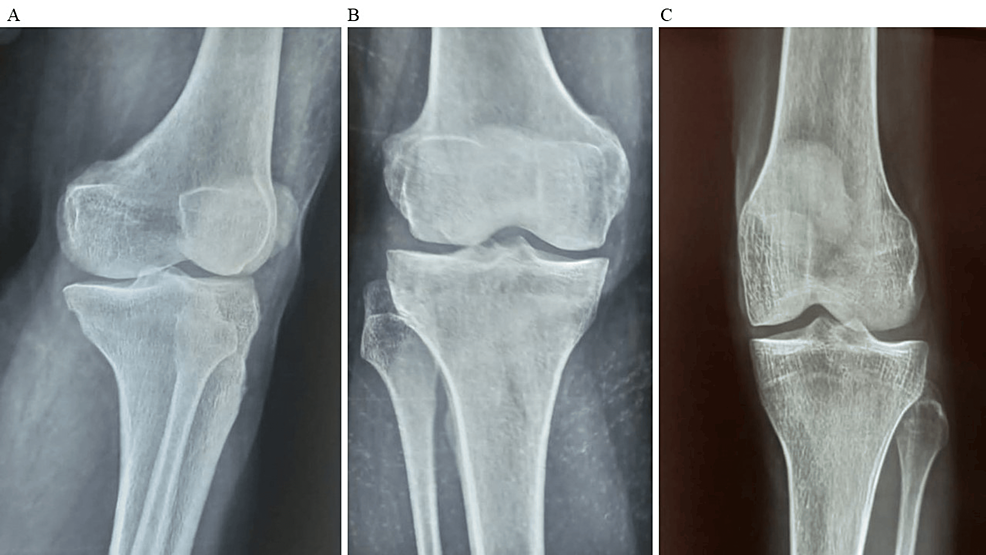

平均WOMAC评分从基线时的56.8±11.5下降到六个月时的41.2±10.6。此外,还监测了不良事件的发生情况,报告了七起不良事件,占参与者的28.0%。这些发现强调了该治疗在六个月内减轻疼痛和改善功能结果方面的有效性。下图2显示了开始干细胞治疗后骨骼的侧视图和前后视图。